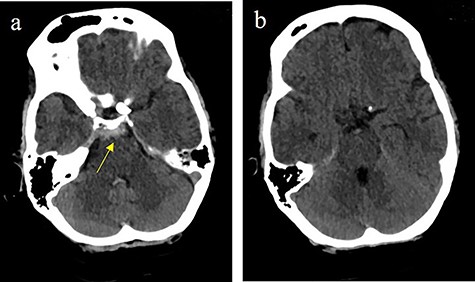

Massive progress of SAH axial cCT at the level of (a) prepontine cistern (arrow) and (b) pentagonal cistern (arrow)

On the next day (Day 9 post-op), the patient suffered from acute and devastating headaches, with screaming and enuresis. An emergency computed tomography (CT) was carried out and displayed a prepontine and retroclival subarachnoid hemorrhage (Hunt & Hess Grade I), (Fig. 2). For further evaluation, a digital subtraction angiography (DSA) was conducted, and it showed a pseudoaneurysm of ophthalmic1/supraclinoid2/C23 part of the left ICA, which was directly treated by a flow diverter (Derivo®—4,5/20), with remaining rest flow (Fig. 3). The patient was transferred to the ICU, transcranial doppler sonography was performed and revealed normal flow. In the following course, the patient suffered from Terson’s syndrome and hyponatremia due to SIADH, but after clinical improvement, was transferred back to normal station after 10 days of post-operative monitoring. Furthermore, the patient was plagued with cephalgia and nausea, which could not be compensated with analgetics and antiemetics. On the 20th post-operative day after the epileptic seizure with postictal vigilance reduction, an emergency CTA was conducted showing progressive SAH (Fig. 4) and a growing pseudoaneurysm as well as generalized vasospasm with posthemorrhagic hydrocephalus. For an emergency CSF diversion, an external ventricle drain was placed. The repeated DSA showed a growing false aneurysm which was treated with two additional flow diverters (2× Derivo®—4,5/20) as well as coiling (HydroSoft™ 2/3 and 2× 1,5/2) by endoleak (Fig. 5). The vasospasms were treated by an intraarterial spasmolysis (Fig. 6).